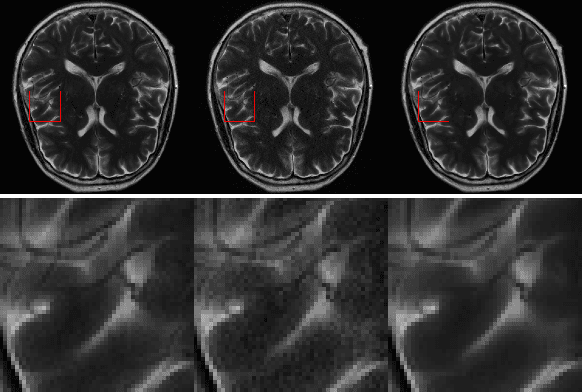

Abstract:k-space undersampling is a standard technique to accelerate MR image acquisitions. Reconstruction techniques including GeneRalized Autocalibrating Partial Parallel Acquisition(GRAPPA) and its variants are utilized extensively in clinical and research settings. A reconstruction model combining GRAPPA with a conditional generative adversarial network (GAN) was developed and tested on multi-coil human brain images from the fastMRI dataset. For various acceleration rates, GAN and GRAPPA reconstructions were compared in terms of peak signal-to-noise ratio (PSNR) and structural similarity (SSIM). For an acceleration rate of R=4, PSNR improved from 33.88 using regularized GRAPPA to 37.65 using GAN. GAN consistently outperformed GRAPPA for various acceleration rates.